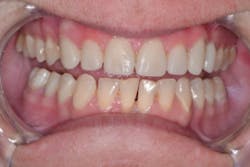

I knew Sarah when she was well and could smile at the world. Then, when the painful loss of a loved one dismantled her life, having no safety net or support, depression set in. Later, substance abuse took over, and eventually Sarah hit rock bottom. Thankfully, a local family took her in, and she is reclaiming her life. But her teeth and smile were devastated (figures 1 and 2).